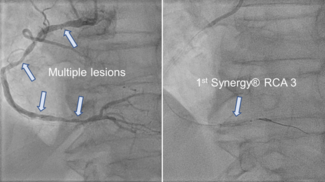

To the authors’ knowledge, this case report is the first to show two giant, partially thrombosed aneurysms of such enormous dimensions presenting as late ST-elevation infarction in the right coronary artery.